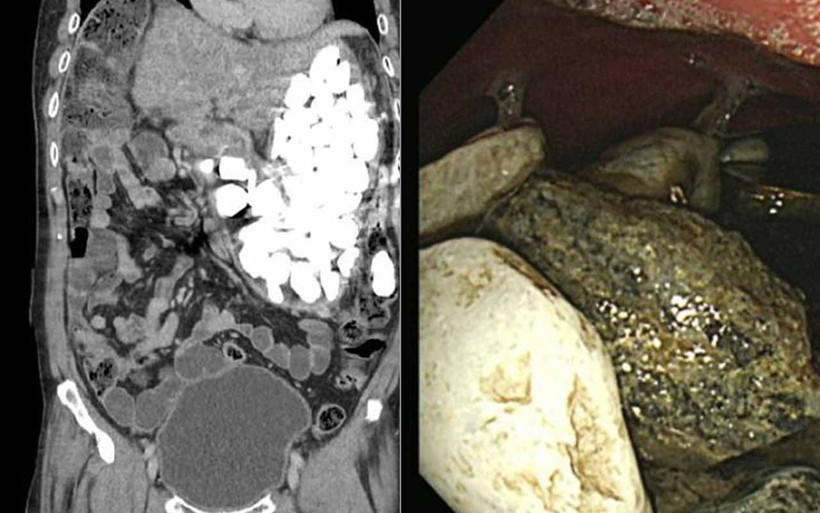

Doktorlar elle yaptıkları muayenelerinde de küçük taşlar hissettiklerini söylediler. Operasyonun ardından adamın midesinden iki kilogram ağırlığında taş, şişe kapağı ve bozuk para çıkarıldı. Tüm olaylardan sonra asıl ilginç olan ise adamın yaptığı açıklama oldu.

Adam daha sonra yaptığı açıklamada anksiyete ile savaştığını ve ilaç almak yerine bazen sakinleşmek için çakıl taşı yuttuğunu itiraf etti.